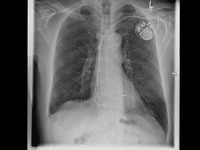

Eine minimalinvasive Herzklappenintervention kann besonders für Risikopatienten infrage kommen.

Für diese Patienten kommt eine minimalinvasive Herzklappenintervention (https://kardiologie-diakonie-siegen.de/kardiologie-fakten-zur-minimalinvasiven-herzklappenintervention/) infrage. Dabei ist keine Herzoperation mit Verwendung einer Herz-Lungen-Maschine notwendig. Stattdessen findet der Eingriff mittels Katheter über die Leistenvene statt. Über den Katheter, einen dünnen Kunststoffschlauch, wird ein Clip zum Herzen geführt. Dabei können die Segel der Mitralklappe mit einem MitraClip bzw. der Trikuspidalklappe mit einem TriClip gefasst und geclippt werden. Dadurch halten die Segel wieder zusammen und die Undichtigkeit der Klappen wird deutlich reduziert. Während der Untersuchung wird unter Narkose eine kontinuierliche Überwachung mit Ultraschall, einer transösophagealen Echokardiographie, durchgeführt. Dadurch können die Clips jederzeit geortet und optimal platziert werden.